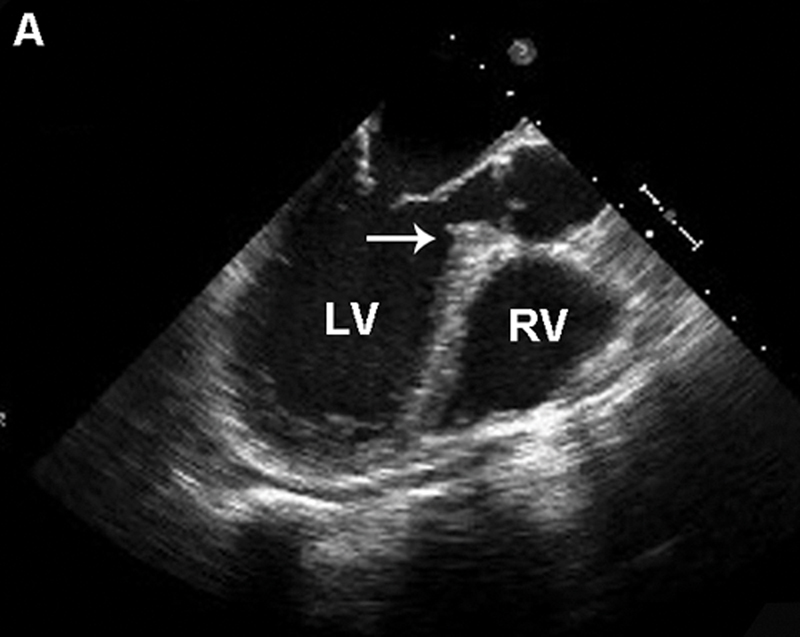

فحوصات تشخيصية لبعض امراض القلب والشرايين التاجية